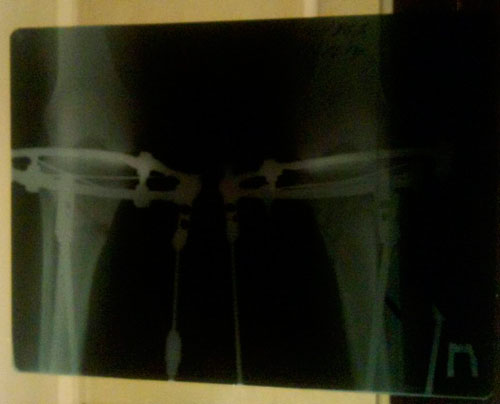

Здравствуйте, Кенже! Качество копии снимков отвратительные - это первое. Во вторых, Вы являетесь нашей пациенткой и обязаны высылать рентген снимки нашей клинике. А хирургу, у которого Вы наблюдаетесь, если и надо сравнивать, пусть оставляет в электронном виде. Ждём снимки в оригинале! Продолжаем сращение.Через почту снимок отправить не получилось, потому что участковый хирург у которого я сейчас наблюдаюсь, попросил сохранить снимок для того, чтобы сравнить его с последующими.Скидываю по несколько вариантов снимки, надеюсь они будут вам понятны . Рентгеновский снимок от 26ноября 2014года. Жду ваших комментариев.

Дата операции 25.09.2014г.

Дата снятия аппаратов 18.03.2015г.

Срок лечения 170 дней.